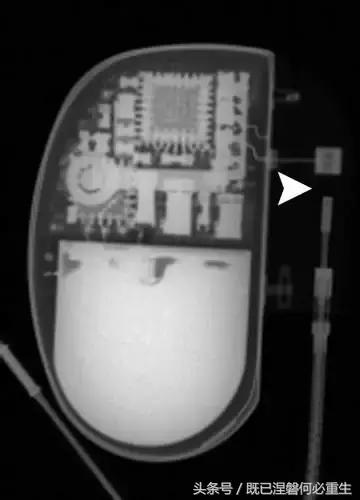

图 1A B 在75岁男性中植入式心律转复除颤器(ICD)的正常部件。

A,额叶胸片显示Medtronic(公司名字)单室ICD。 ICD的基本组件包括发生器,导线和围绕右心室(RV)导线的冲击线圈。 该系统还具有上腔静脉(SVC)中的冲击线圈,其可能不存在于所有系统中。 起搏器没有冲击线圈。 铅固定(见图8A)固定到胸部,并且可能或可能不在胸部X光片上可见。

B,引线通过头连接到发电机(黄色),其保持一个或多个连接端口。 所示系统需要三个端口(一个用于双极起搏或感测元件,一个用于RV休克线圈,一个用于SVC冲击线圈)。 正确放置的引脚将延伸超出连接器(见图9)。 制造商的标志和单个设备标识符的字体被反转,因为发电机被定向以允许在发生器口袋中适当的引线盘绕。 这种定位被设计成减少扭结的风险,这可能导致断裂。 有关制造商徽标的更多信息,请参见图4。